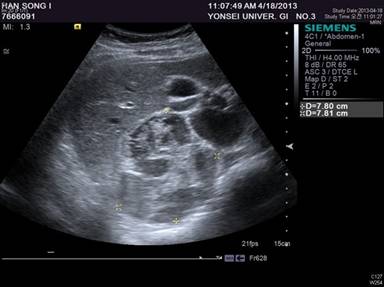

A 27-year-old woman with no significant past medical history was referred to our institution for evaluation of an abdominal mass in the right upper quadrant. The mass was discovered on ultrasonography when she visited a gastroenterologist for vague epigastric discomfort and vomiting that had persisted for one month. At the time of presentation, she denied any possibility of pregnancy; therefore, further examinations proceeded without any obstetric concerns. On physical examination, the abdomen was soft and the mass was not palpable, but she complained of direct tenderness in the right upper quadrant. The laboratory tests were within normal limits, and the endocrinologic examinations did not show any features suggestive of adrenal endocrinologic dysfunction. Ultrasonography demonstrated a 7.8 x 7.8 cm clearly demarcated mass in the right adrenal gland with heterogeneous echogenicity and cystic portions (Figure 1).

Figure 1. Abdominal ultrasonography showed a multiloculated cystic lesion in the right adrenal region, measuring 7.8 x 7.8 centimeters. |